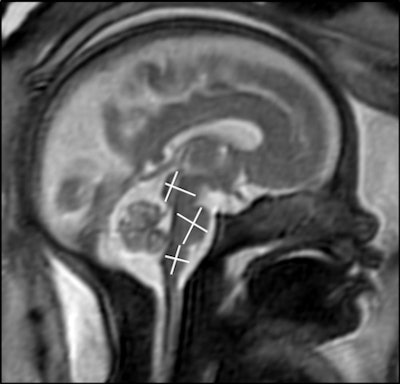

A research team led by Dr. Sophia Stöcklein from the Ludwig Maximilian University of Munich in Germany used MRI to show that fetal brains had age-appropriate developments even as their expectant mothers presented with mild to moderate COVID-19 symptoms. Image courtesy of the RSNA.The team found that brain development characteristics, such as opercularization of the Sylvian fissure, cortical folding, and transverse cerebellar diameter were age-appropriate in all fetuses. They also found that the diameter and craniocaudal extent of the pons, medulla oblongata, midbrain, and cerebellar vermis were all within age-appropriate limits.

"No calcifications, edema, or ventricular enlargement were detected. Seven fetuses showed mild asymmetry of the lateral ventricles with a maximum difference of 4 mm," they wrote.